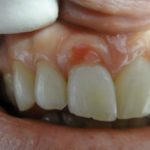

Если свищ поразил ткани слишком сильно, назначается операция. Это часто происходит при установке коронки, или когда в резце стоит штифт – лучше сразу удалить свищ, чем демонтировать такие конструкции, а затем их восстанавливать. Сегодня практически во всех клиниках используется лазерный метод удаления образований без боли и с более быстрым заживлением тканей. Поэтому если врач рекомендует операцию, стоит прислушаться к его мнению. Он также порекомендует, чем полоскать свищ на десне для более быстрого заживления. Будьте здоровы и лечитесь своевременно.